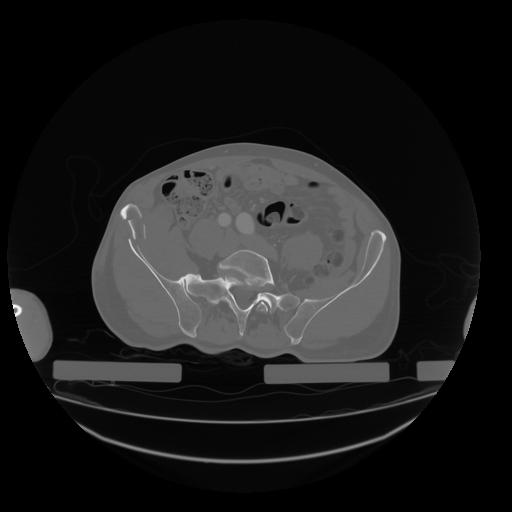

28 CUERPO,CE,Vol,2.0,CUERPO,,